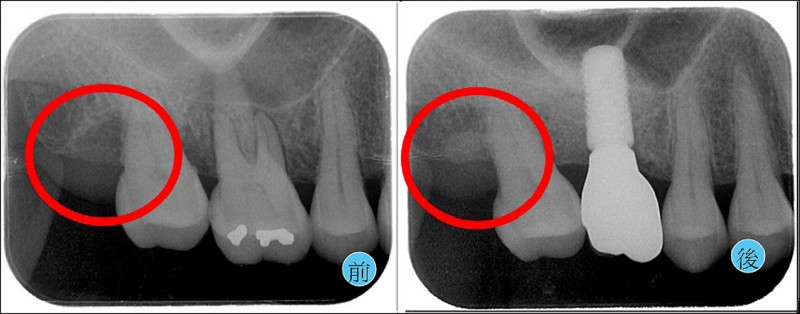

牙周囊袋深度已經降低至健康的2-3毫米,定期回診追蹤(圖2)。